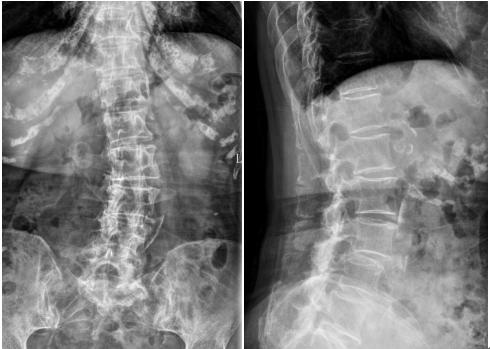

▲术前X线显示脊柱侧弯、腰椎滑脱、腰椎不稳定

庄女士因“间断腰痛30余年,近半年加重伴右下肢疼痛麻木行走困难”入院。术前检查示腰椎管狭窄、腰椎滑脱、脊柱侧弯、腰椎间盘突出、腰椎不稳等多种病变,神经受压严重,病情复杂。在接诊后,医院脊柱外科(骨四科)高度重视患者治疗情况,为患者量身定制手术方案。在全面评估患者情况,并与患者及家属充分沟通征得同意后,脊柱外科(骨四科)团队决定采用腰椎后路椎板部分切除减压棘突间内固定装置置入术为患者减轻病痛。